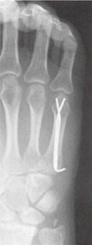

鏡視下バンカート&ブリストウ法術後のレントゲン・CT

骨を移植することでより強固に脱臼を制動する手術です。鏡視下バンカート法を行っても再発した場合や、ラグビー・アメリカンフットボール・柔道などのコンタクトスポーツ選手、自衛隊員・レスキュー隊員などの危険業務に携わる方の場合にはこちらを行います。競技までの復帰が早いことも特徴です。

骨で抑える事ができるようになり再脱臼率が低下します。

手術方法

鏡視下バンカート修復術にブリストウ法という骨を移行する手術を追加します。

・烏口突起(骨)を腱をつけたまま切る。

・烏口突起を関節窩の前にスクリューで固定。

・鏡視バンカート修復術を行います。